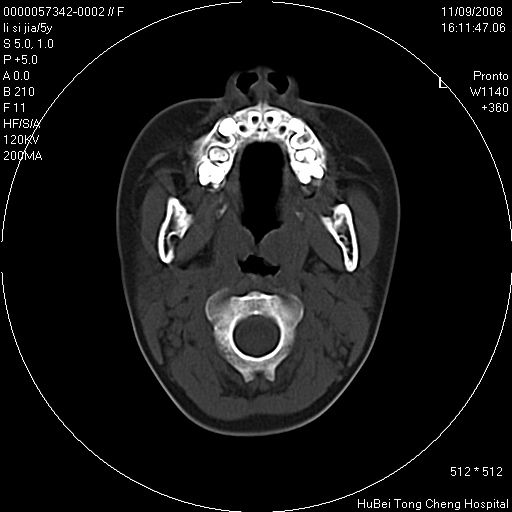

患儿 女,5岁。鼻塞、流涕2年余。

临床诊断:慢性副鼻窦炎?

副鼻窦ct轴位平扫(层厚、层距均为5mm),图像如下:

双侧上颌窦\\筛窦及蝶窦内均可见多量软组织密度影,结合病史支持考虑慢性全鼻窦炎

双侧上颌窦、筛窦及蝶窦内均可见粘膜增厚,结合病史支持考虑慢性全付鼻窦炎,腺样体肥大。